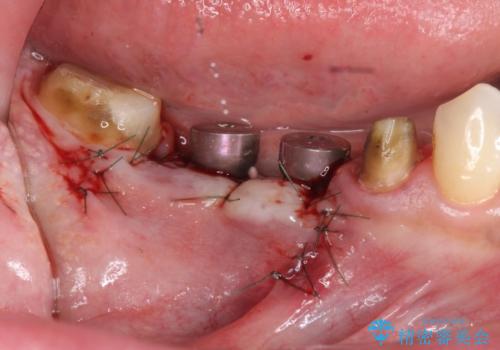

長いブリッジをインプラント補綴への変更

支台を増やし、残った歯の負担を減らし守るために欠損部位にインプラントを埋入し咬合力の負担に対応できる環境を整えます。

- 105.4万円(仮歯×4・ストローマンインプラント×2・チタンカスタムアバットメント×2・ジルコニアクラウン×4)費用は治療当時の料金となります

インプラント治療は、ブリッジや入れ歯と異なり人口の歯根となるインプラントを顎骨内に埋入することで咬合力に耐える支台を増やせるというメリットがあります。

残った歯の負担を減らすことでより長期的な予後を期待することができます。